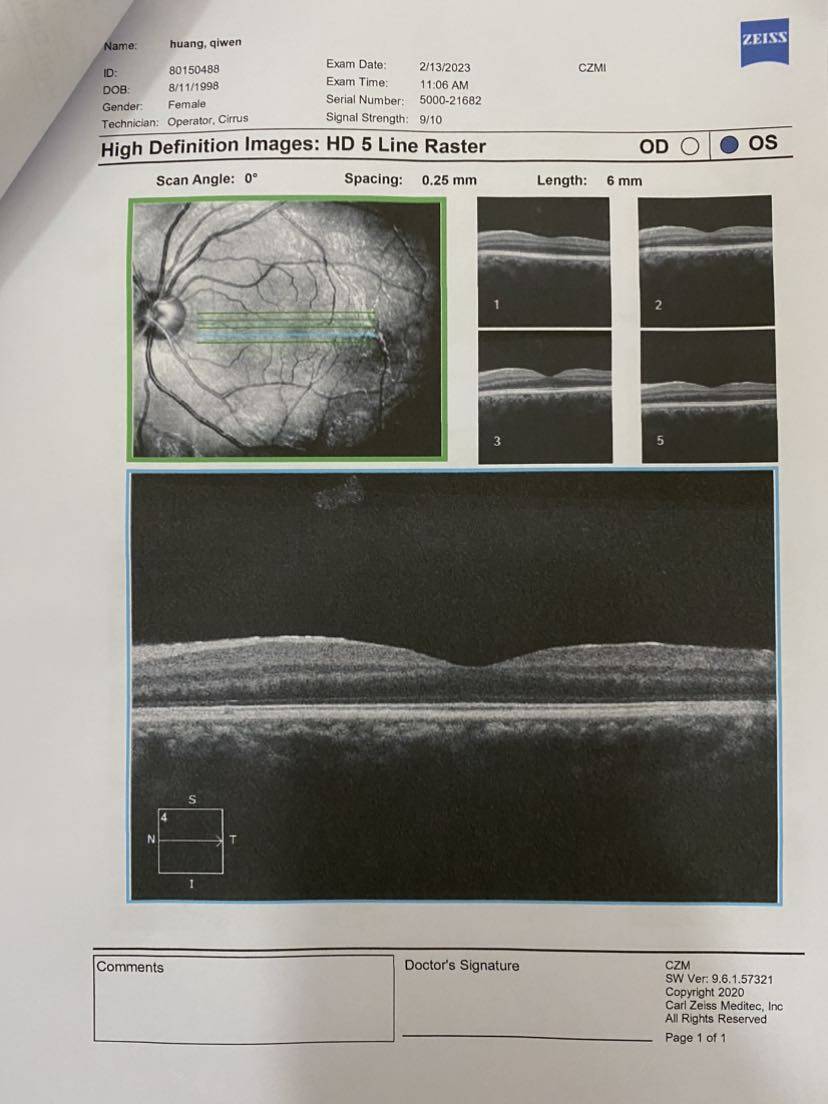

翻开第一页就说,视网膜很明显有问题。 说是什么前膜,说目前还没影响到黄斑(?),不影响视力,但如果后期发展拉扯到黄斑看东西就会变形……然后听不懂😂

说是什么前膜,说目前还没影响到黄斑(?),不影响视力,但如果后期发展拉扯到黄斑看东西就会变形……然后听不懂😂

说是什么前膜,说目前还没影响到黄斑(?),不影响视力,但如果后期发展拉扯到黄斑看东西就会变形……然后听不懂😂

说是什么前膜,说目前还没影响到黄斑(?),不影响视力,但如果后期发展拉扯到黄斑看东西就会变形……然后听不懂😂一开始挺凝重的,然后我说我有狼疮,医生好像就淡定了?!?

最后把所有报告记录一下,医生说要保管好。千万不能折,那就拍照先留个底吧~

【眼部ct】